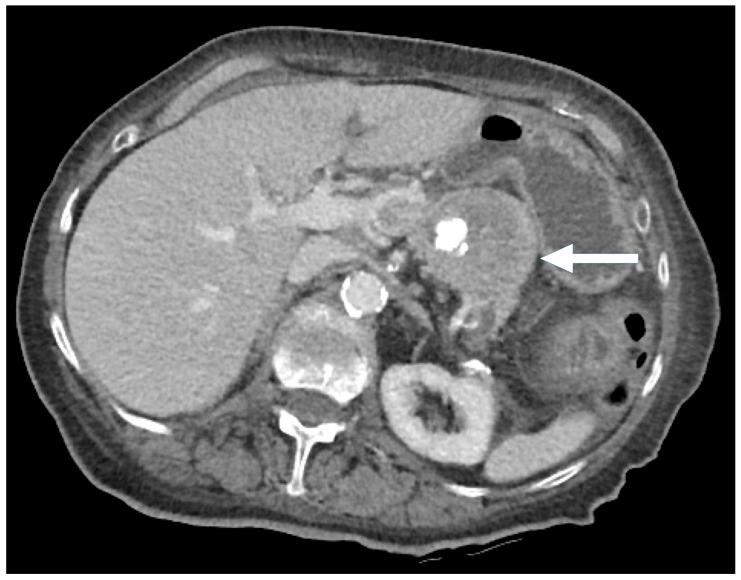

Pancreatic neuroendocrine neoplasms (PNENs) are rare but clinically significant tumors with variable radiological presentations that complicate diagnosis. While typical PNENs are well characterized, atypical features, such as cystic or hypoenhancing patterns, are less understood and can lead to diagnostic delays or misdiagnosis. This study aimed to evaluate atypical radiological presentations of PNENs, focusing on their impact on diagnostic pathways and differentiation from other pancreatic pathologies. A retrospective review was conducted of all PNEN cases diagnosed at a single tertiary center between 2010 and 2020. Cases with histopathological confirmation and available cross-sectional imaging were included. Radiological features were categorized as typical (solid and hyperenhancing) or atypical (cystic and hypoenhancing). Demographic, radiological, and pathological data were analyzed. Comparisons between typical and atypical PNENs were performed using descriptive and inferential statistics. Among 77 PNEN cases, 39 met the inclusion criteria. Atypical radiological presentations were identified in 46% of cases, including cystic (18%) and hypoenhancing (28%) lesions. Hypoenhancing PNENs were significantly more likely to present with advanced disease (54% vs. 14% in typical PNENs, = 0.016). In contrast, none of the cystic PNENs exhibited advanced disease. Atypical PNENs posed greater diagnostic challenges, with alternative diagnoses initially considered in 64% of hypoenhancing and 43% of cystic cases compared to 10% of typical PNENs ( = 0.0042). Atypical PNENs, particularly hypoenhancing lesions, present significant diagnostic challenges and are more likely to be associated with advanced disease. These findings highlight the need for improved recognition of atypical imaging patterns and more precise diagnostic strategies. However, the retrospective design and small cohort size limit the generalizability of our findings. Further multicenter studies are warranted to refine the imaging criteria and optimize the differentiation from other pancreatic neoplasms.

胰腺神经内分泌肿瘤(PNENs)虽罕见,但具有临床意义,其放射学表现多样,使诊断变得复杂。典型的PNENs特征明确,但非典型特征,如囊性或强化减弱模式,了解较少,可能导致诊断延迟或误诊。本研究旨在评估PNENs的非典型放射学表现,重点关注其对诊断途径的影响以及与其他胰腺病变的鉴别。对2010年至2020年在单个三级中心诊断的所有PNEN病例进行了回顾性研究。纳入有组织病理学证实且有横断面影像资料的病例。放射学特征分为典型(实性且强化明显)或非典型(囊性且强化减弱)。对人口统计学、放射学和病理学数据进行分析。使用描述性和推断性统计对典型和非典型PNENs进行比较。在77例PNEN病例中,39例符合纳入标准。46%的病例发现有非典型放射学表现,包括囊性病变(18%)和强化减弱病变(%)。强化减弱的PNENs出现晚期疾病的可能性显著更高(54%,而典型PNENs为14%,P = 0.016)。相比之下,囊性PNENs均未出现晚期疾病。非典型PNENs带来更大的诊断挑战,与典型PNENs的10%相比,64%的强化减弱病例和43%的囊性病例最初考虑了其他诊断(P = 0.0042)。非典型PNENs,尤其是强化减弱病变,带来显著的诊断挑战,且更可能与晚期疾病相关。这些发现凸显了提高对非典型影像模式的认识以及采用更精确诊断策略的必要性。然而,回顾性设计和小样本队列限制了我们研究结果的普遍性。有必要进行进一步的多中心研究以完善影像标准并优化与其他胰腺肿瘤的鉴别。